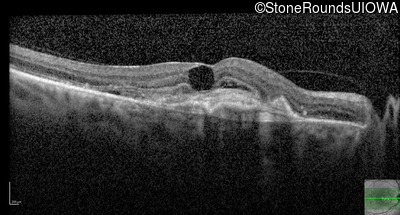

AR Stargardt Disease (IIA)

Age at visit: 59 years (Visit 3)

This 59 year old woman first noticed vision loss in her right eye a few months earlier. She has a cousin with Rhodopsin-associated RP.

Diagnosis & molecular findings

Disease Gene Allele 1 variant(s) Allele 2 variant(s) Inheritance mode

AR Stargardt Disease ABCA4 Arg219Thr AGA>ACA Gly863Ala (G)GA>(G)CA AR